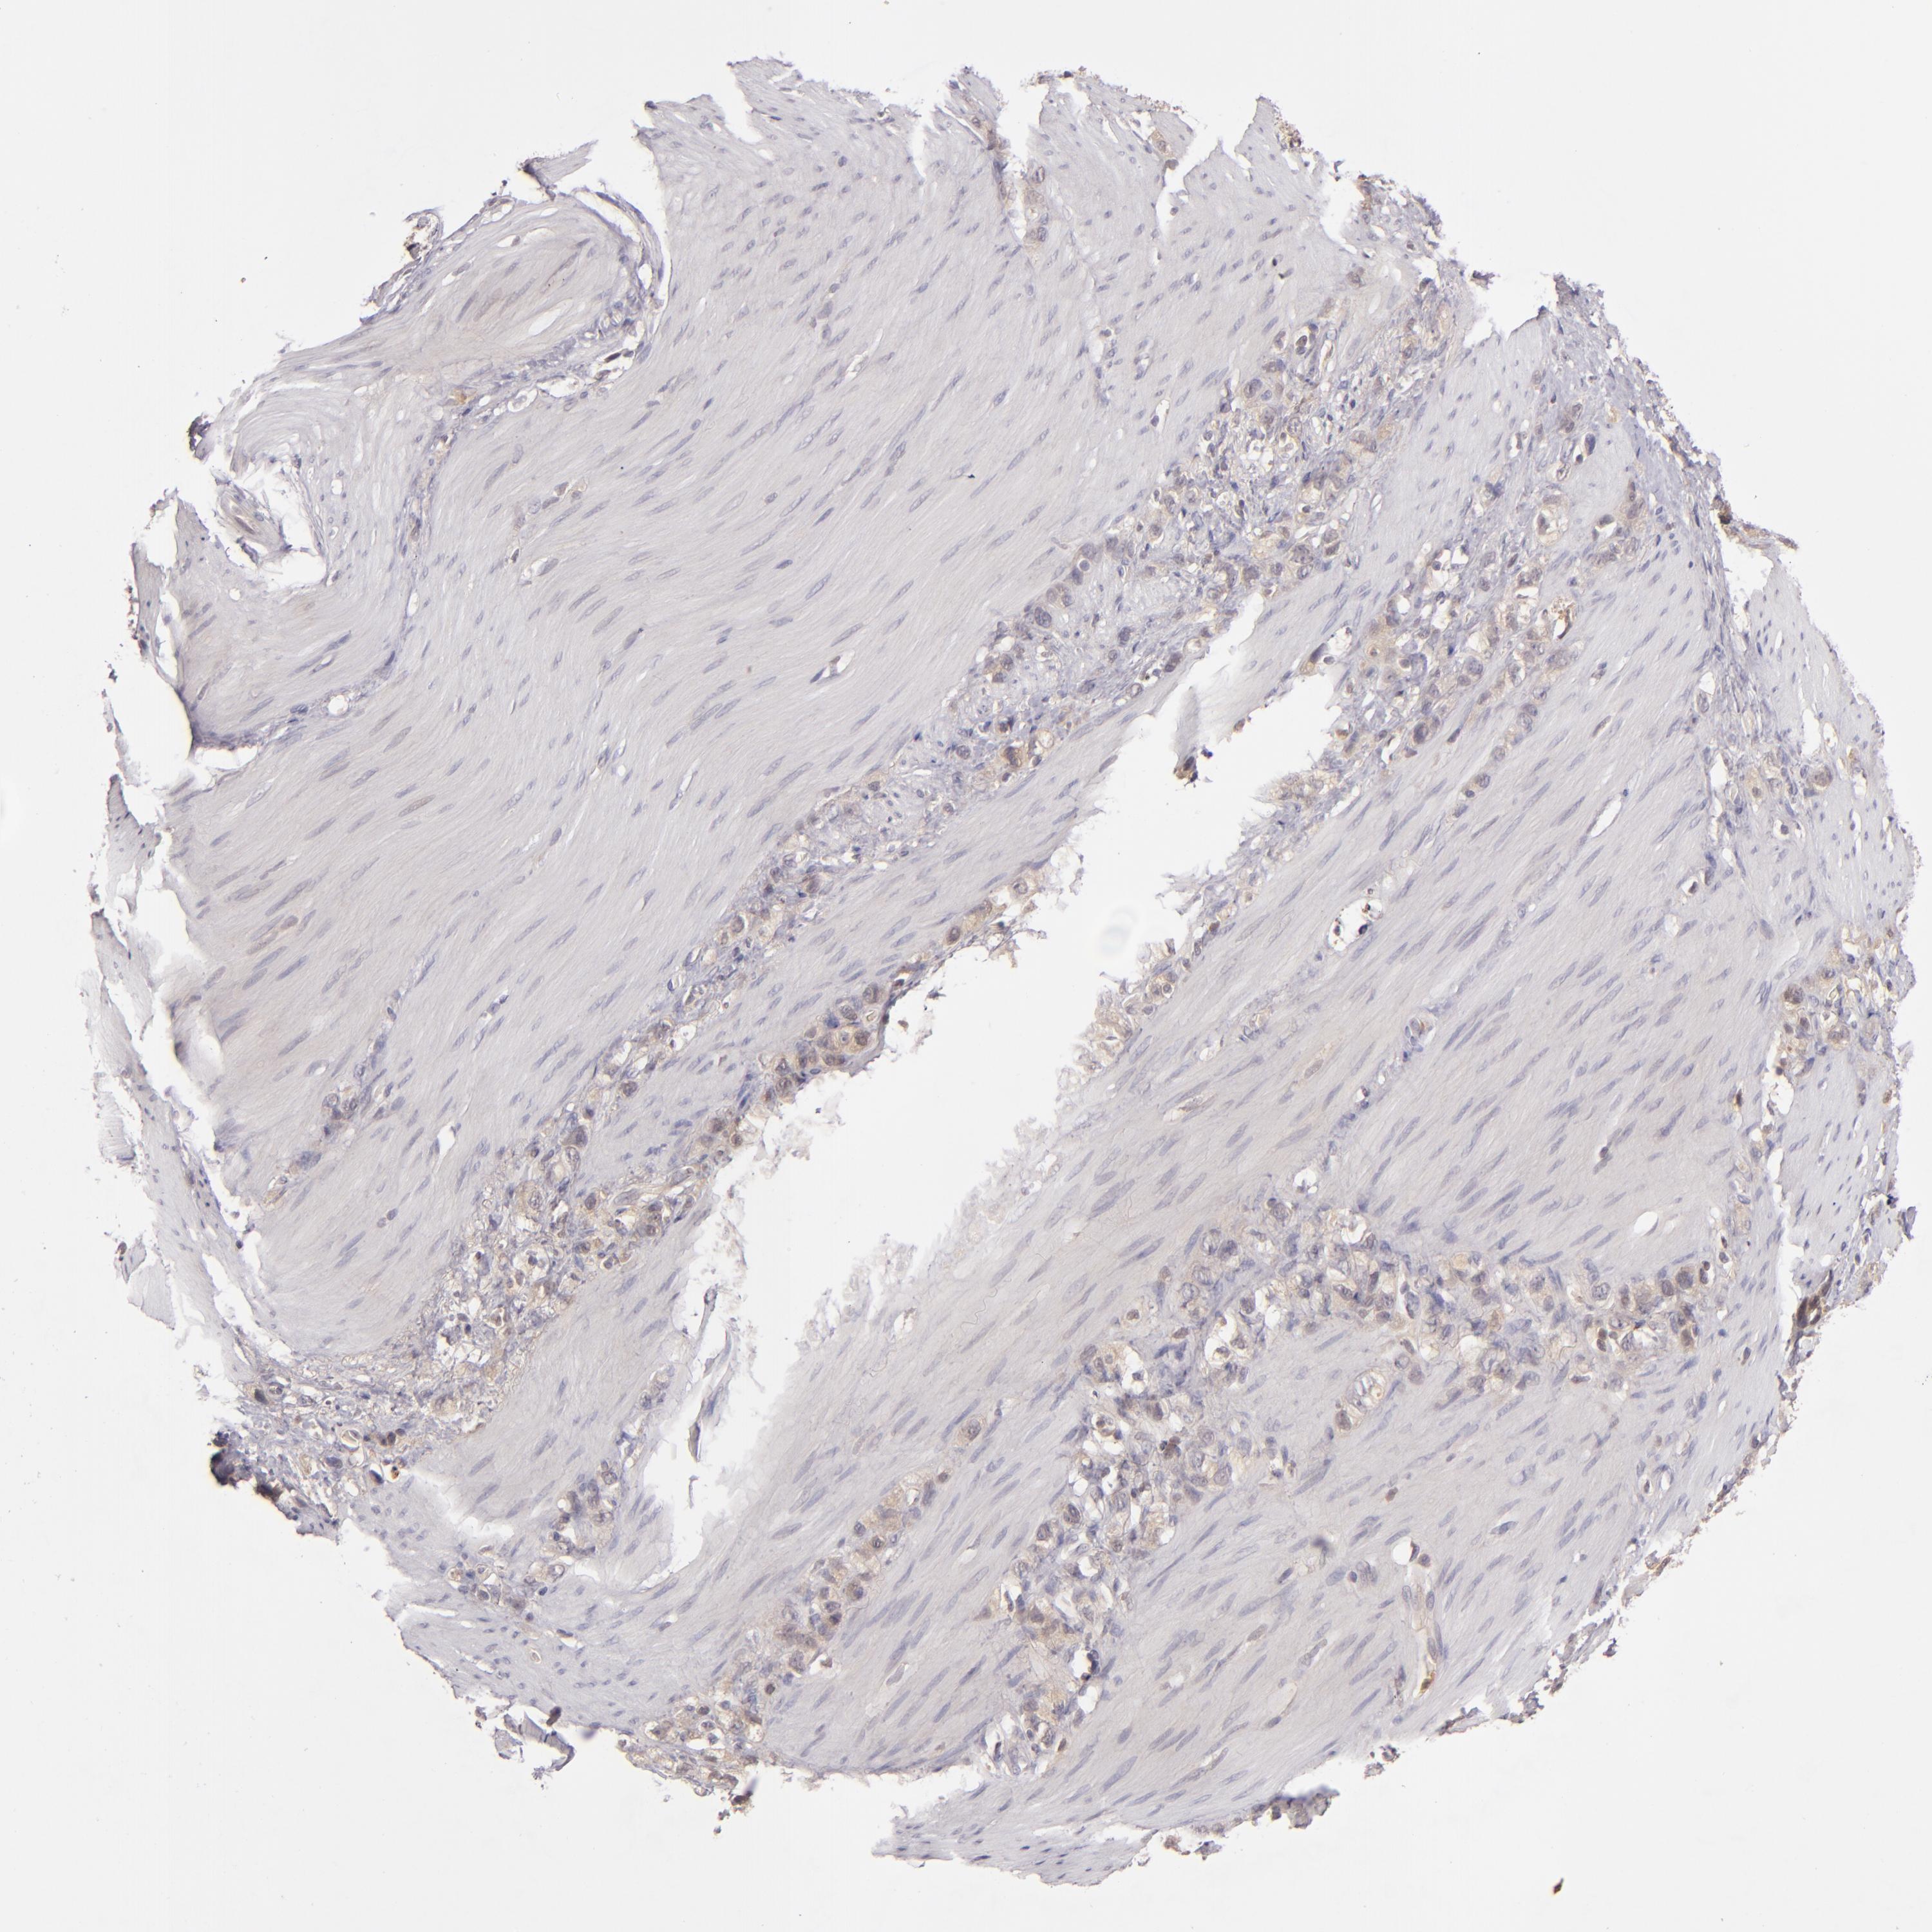

STOMACH CANCER - Protein expressioni

A mouse-over function shows sample information and annotation data. Click on an image to view it in a full screen mode. Samples can be filtered based on level of antibody staining by selecting one or several of the following categories: high, medium, low and not detected. The assay and annotation is described here.

Note that samples used for immunohistochemistry by the Human Protein Atlas do not correspond to samples in the TCGA dataset.

Antibody stainingi

Antibody staining in the annotated cell types in the current human tissue is reported as not detected, low, medium, or high, based on conventional immunohistochemistry profiling in selected tissues. This score is based on the combination of the staining intensity and fraction of stained cells.

Each image is clickable and will lead to virtual microscopy that enables deeper exploration of all samples and also displays staining intensity scores, fraction scores and subcellular localization as well as patient and tissue information for each sample.

Antibody HPA001888

Antibody HPA001889

Staining

High

Medium

Low

Not detected

Intensity

Strong

Moderate

Weak

Negative

Quantity

>75%

75%-25%

<25%

None

Location

Nuclear

Cytoplasmic/membranous

Cytoplasmic/membranous,nuclear

Adenocarcinoma, NOS

Adenocarcinoma, High grade